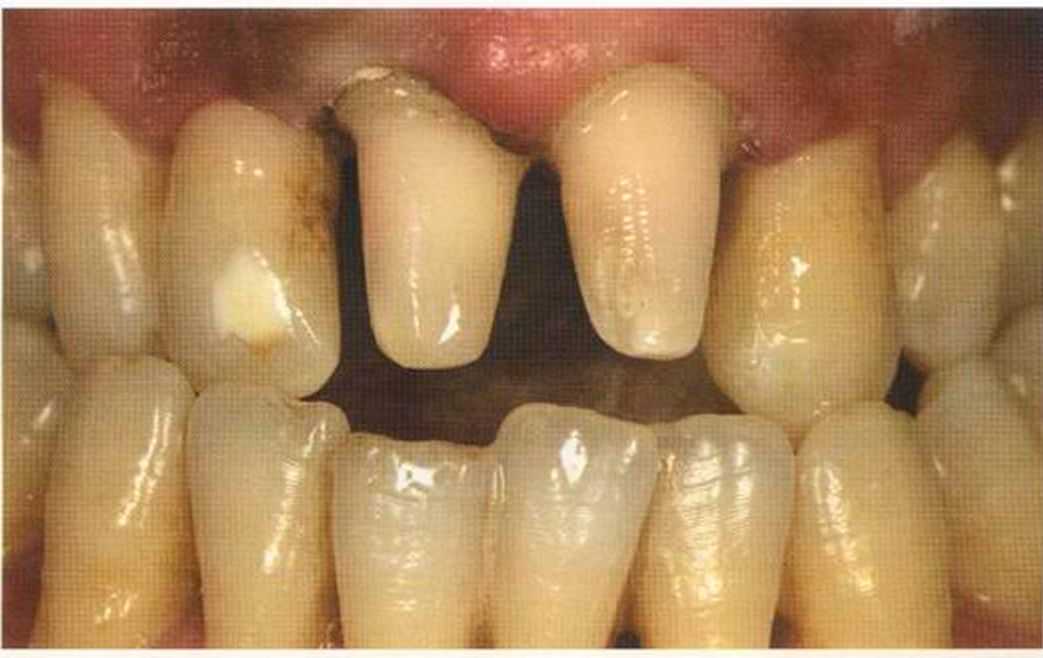

Первое лечение проходию много лет назад у другого доктора. Со временем ос те пи / ка уху дин ьась, особенно в пришеечной области. Этот пациент хотел новые коронки в области 12 и 22, по сомневсься, нас кол ько хорошо они будут выглядеть.

Результат с использованием In-Ceram развеял все сомнения, и решение об изготовлении коронки на другой боковой резец не заставило себя долго ждать.

После того как мы определит цвет зуба, решено быо сначсьа изготовить одну коронку.

Безметалловые реставрации также отлично подходят для пациеьипов с непереносимостью всех металлов. У этого пациента положительная аллергологическая проба даже на сплавы с высоким содержанием золота.

Так как 21 зуб депульпирован, и культя не подходит для изготовления коронки, была изготовлена культевая вкладка из Zirconia. Эта методика очень дорогая, но в данном случае были все показания для ее применения.

Го то вый результат. Зуб 21 со штифтом из Zirconia. От 12 до 21 изготовлены три отдел1>ные коронки 1п-Сегат. Все зафиксировано в полости рта на цемент Panavia ТС.